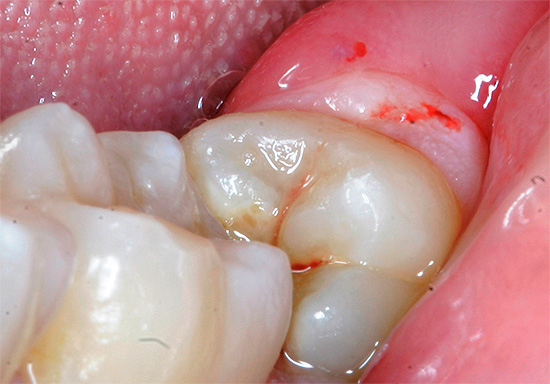

Dopo alcuni giorni, può verificarsi la pericoronite purulenta, che è caratterizzata da un forte e costante dolore dietro la saggezza dei "sette" adiacente al dente. Può comparire dolore che penetra nell'orecchio e nella tempia e si avverte anche quando si deglutisce come una "mal di gola dentale". Sullo sfondo dell'infiammazione locale, la temperatura corporea sale a circa 37,5 gradi e l'apertura della bocca viene interrotta.

I linfonodi sottomandibolari si allargano e diventano dolorosi alla palpazione. Con la pressione sul cappuccio, il pus viene rilasciato - la causa di tutte le sofferenze. Sullo sfondo di un dente del giudizio in eruzione difficile, vengono visualizzati arrossamento e gonfiore del tessuto della guancia adiacente, arco palato-linguale e palato molle.

La fase acuta dell'infiammazione con alti livelli di difesa immunitaria e la rottura del pus nella cavità orale possono trasformarsi in una forma cronica lenta, ma dopo un certo periodo si verifica di solito un'esacerbazione. A causa di una violazione del deflusso di pus, può verificarsi una periostite post-molare con gravi fenomeni di intossicazione: un aumento della temperatura corporea a 38,5 con l'incapacità di masticare il cibo sullo sfondo della difficoltà ad aprire la bocca.